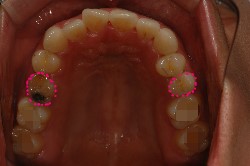

연두색으로 동그라미 친 위 왼쪽 하나, 아래 양쪽 하나씩

게다가 위쪽에 잇는 유치는 공기주머니가 치아뿌리 바로 위까지 내려와 잇어서

아까 보앗던 입속사진을 다시 보면

왼쪽 동그라미가 유치고 오른쪽 동그라미는 영구치에요

크기 차이가 보이시나요??

작은 영구치가 나야할 자리를 커다란 유치가 차지하고잇으니 치열이 앞으로 밀려나오게 된거래요